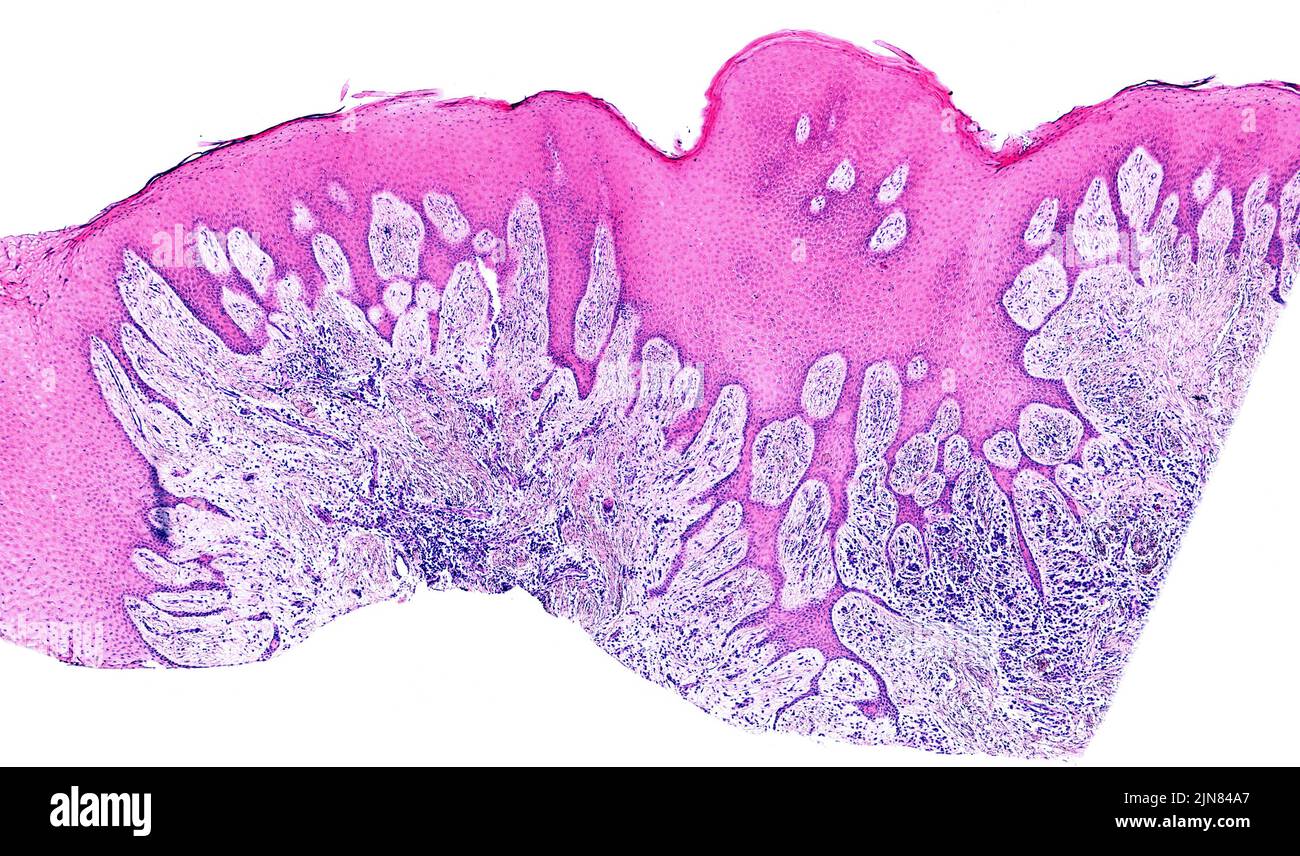

Gingivitis, light micrograph Stock Photo Alamy Light Gingivitis Just a few key steps can improve your gum health. Find out how to spot the first signs of gingivitis & the best ways to treat it. The main symptom of gingivitis is red, puffy gums that may bleed when a person brushes their teeth. View the gingivitis cheat sheet. Diagnosis is based on inspection. Gingivitis is a common and. Light Gingivitis.

Gingivitis, light micrograph Stock Image F002/9208 Science Photo Light Gingivitis View the gingivitis cheat sheet. Diagnosis is based on inspection. It develops when plaque, tartar and bacteria build up on your teeth, causing red, swollen, bleeding gums. Gingivitis is a type of periodontal disease characterized by inflammation of the gums (gingivae), causing bleeding with swelling, redness, exudate, a change of normal contours, and, occasionally, discomfort. Gingivitis is caused by bacterial. Light Gingivitis.

Gingivitis, Light Micrograph Photograph by Steve Gschmeissner Light Gingivitis Diagnosis is based on inspection. Gingivitis is a common and mild form of gum disease that causes irritation, redness and swelling of your gums. It develops when plaque, tartar and bacteria build up on your teeth, causing red, swollen, bleeding gums. Find out how to spot the first signs of gingivitis & the best ways to treat it. Treatment involves. Light Gingivitis.